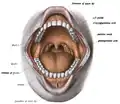

The alveolar process (/ælˈviːələr, ˌælviˈoʊlər, ˈælviələr/)[1] or alveolar bone is the thickened ridge of bone that contains the tooth sockets on the jaw bones (in humans, the maxilla and the mandible).[2] The structures are covered by gums as part of the oral cavity.

The synonymous terms alveolar ridge[3] and alveolar margin are also sometimes used more specifically to refer to the ridges on the inside of the mouth which can be felt with the tongue, either on roof of the mouth between the upper teeth and the hard palate or on the bottom of the mouth behind the lower teeth.[4]

3D animation showing placement of teeth in human skull In the oral cavity, the alveolar processes are covered by gums.

In the oral cavity, the alveolar processes are covered by gums. How the roots of the teeth, gums, and alveolar bone are related